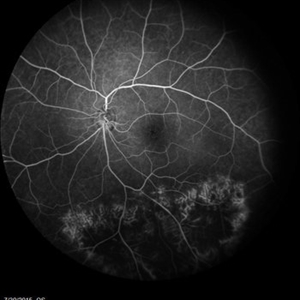

Retinal Dystrophy of 24-Year-Old Male/ Fluorescein Angiogram OS

Nov 25 2015 by Zach Dupureur

Fluorescein angiography of a 24-year-old male. Juvenile retinoschisis on OCT. FA shows outer retinal staining. Could be associated with Goldman Farve Syndrome.

Photographer: Zach Dupureur OCT-C

Imaging device: Heidelberg Spectralis

Condition/keywords: Goldmann-Favre Syndrome, juvenile retinoschisis, retinal dystrophy